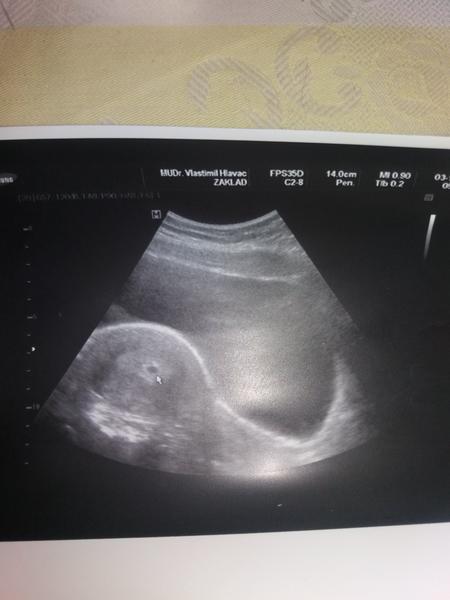

Cauky všem 😉 tak jsem dneska byla na kontrole a jsem b zacatku 4 tyden ..zpozdilé jsme si ovulaci takže jsem otehotnela dyl .ale hned se to zrnko rýže 6mm veliký ukázalo tam kde ma být ..nezapomenutelný okamžik 😊 za dva týdny na další ultrazvuk uz se nemohu dočkat ☺ ps: dělal mi ultrazvuk přes břicho a vše bylo krásné vidět tak každý doktor to dělá jinak .. Vám všem přeji dvě čárečky a krásné tehulkovani 😉